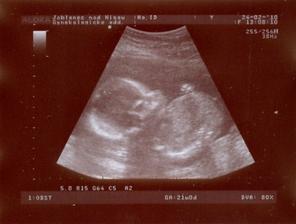

31.12. - velké utz v Gennetu - NT screening (o pár dní dříve nabrána i krev)

Výsledek naprosto v pořádku. Riziko vývojových vad 1:50 000, hodnota NT 1,4, nosní kůstka přítomna 🙂 Odpovídáme 13+4tt, miminko měří 7,5cm a poprvé jsme slyšeli srdíčko 🙂))